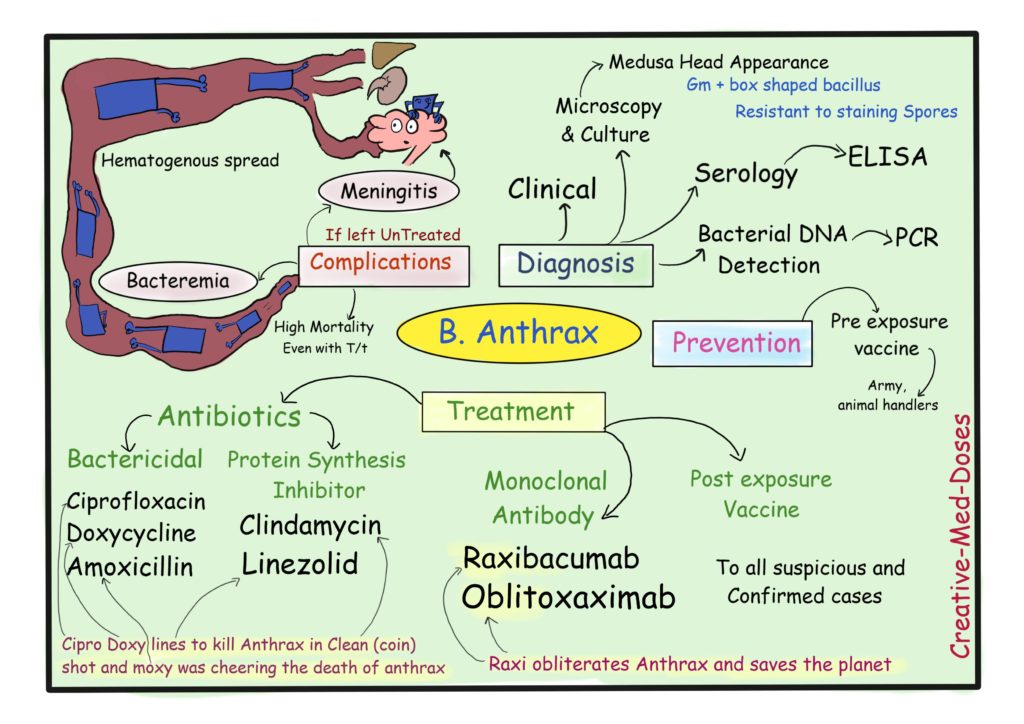

How to cure anthrax. Inhalation anthrax can also be treated with a combination of antibiotics and injections of raxibacumab or obiltoxaximab (monoclonal antibodies that bind anthrax toxins in the. [4] anthrax vaccination is recommended for people at high risk of infection. Inhalational anthrax results from breathing anthrax spores into the lungs.

Doctors have several options for treating patients with anthrax, including antibiotics and antitoxin. While naturally occurring, it remains. [3] immunizing animals against anthrax is recommended in areas where previous infections have.

Types of anthrax the types of anthrax reflect the different ways the bacteria enter your body. Natural ways to cure anthrax white fir. There are other treatments, including a vaccine.

Anthrax is rare, and most people will never be exposed to it. There are two main ways to prevent anthrax: Your doctor will ask you what kind of work you do, along with other questions to determine the likelihood of.

How can anthrax be prevented? Many scholars think that in moses’ time, during the 10 plagues of egypt, anthrax may have caused what was known as the fifth plague, described as a sickness affecting horses,. They may require aggressive treatment, such as continuous fluid drainage and help breathing through.

When the anthrax can’t grow anymore, it dies. Background in a review of treatment in the early days of antibiotics half a century ago, herman gold (1955) wrote: Published on april 29, 2023 medically reviewed by anju goel, md table of contents view all anthrax powder history how do humans encounter anthrax?

Antibiotics work in two main ways, by killing the anthrax or by stopping the anthrax from growing. For people who have been exposed to anthrax (but have no symptoms of the disease), providers may prescribe preventive.